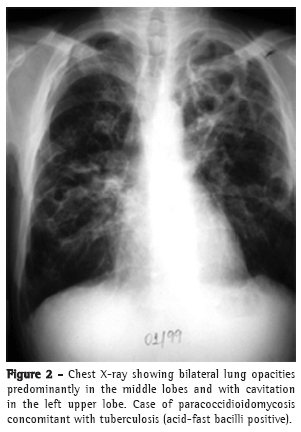

In most cases, the clinical complaints, the physical examination data, and the radiological alterations presented by these patients did not allow a clear distinction to be made between the two diseases in most cases (Figures 2-4).

Pulmonary alterations are typically bilateral, predominantly in the middle lobes and spinal cord regions.(16,17)

In contrast, TB affects males and females of all ages, the majority of whom are symptomatic and present abnormal physical examination findings, as well as radiological alterations, which can also be bilateral but are typically most pronounced in the superior and posterior segments.